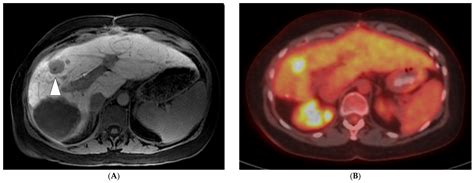

MRI with Contrast Highly sensitive; often used to differentiate benign lesions from metastases.

PET Scan Used to detect metabolic activity and assess for widespread disease.